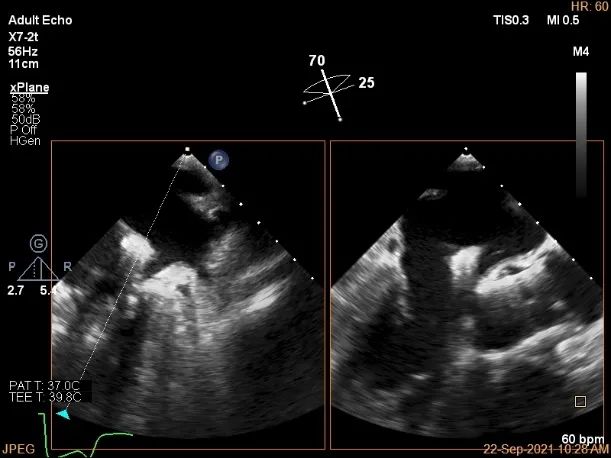

术前超声评估

3D:P1区脱垂并腱索断裂,Width:11.4mm

3D-color:重度MR,4级

麻醉状态下肺静脉血流频谱